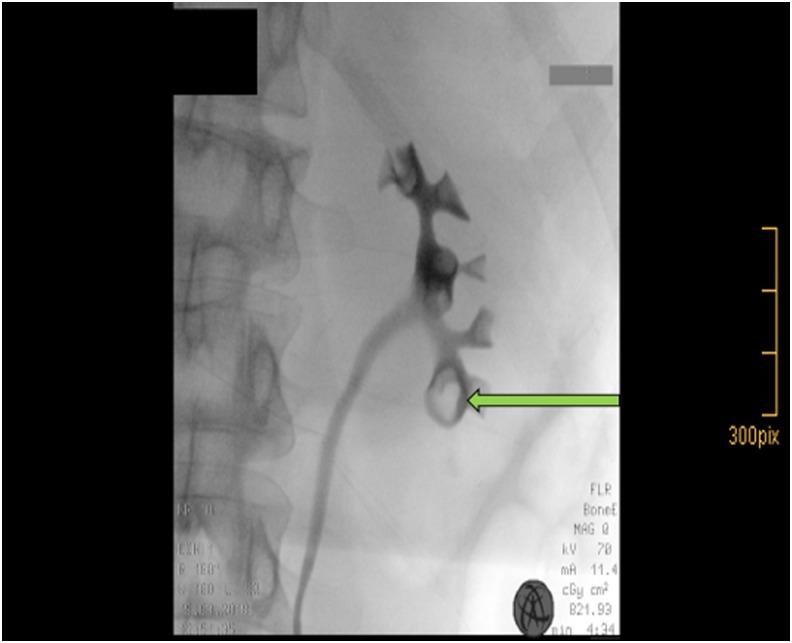

Asymptomatic microscopic hematuria (AMH) is incidentally found during routine health screenings. In the clinical evaluation of persistent AMH imaging modalities, CT urography, MR urography, and retrograde pyelography are of diagnostic importance. In case of pathologic findings (e.g., contrast-filling defects), endoscopic evaluation is mostly performed. To our knowledge, we report the first case of a patient with persistent AMH caused by biopsy-proven renal papillary hyperplasia.

无症状性镜下血尿(AMH)是在常规健康筛查中偶然发现的。在对持续性AMH进行临床评估时,CT尿路造影、磁共振尿路造影和逆行肾盂造影等影像学检查具有诊断意义。如果发现病理结果(如造影剂充盈缺损),大多会进行内镜评估。据我们所知,我们报告了首例经活检证实为肾乳头增生导致的持续性AMH患者。